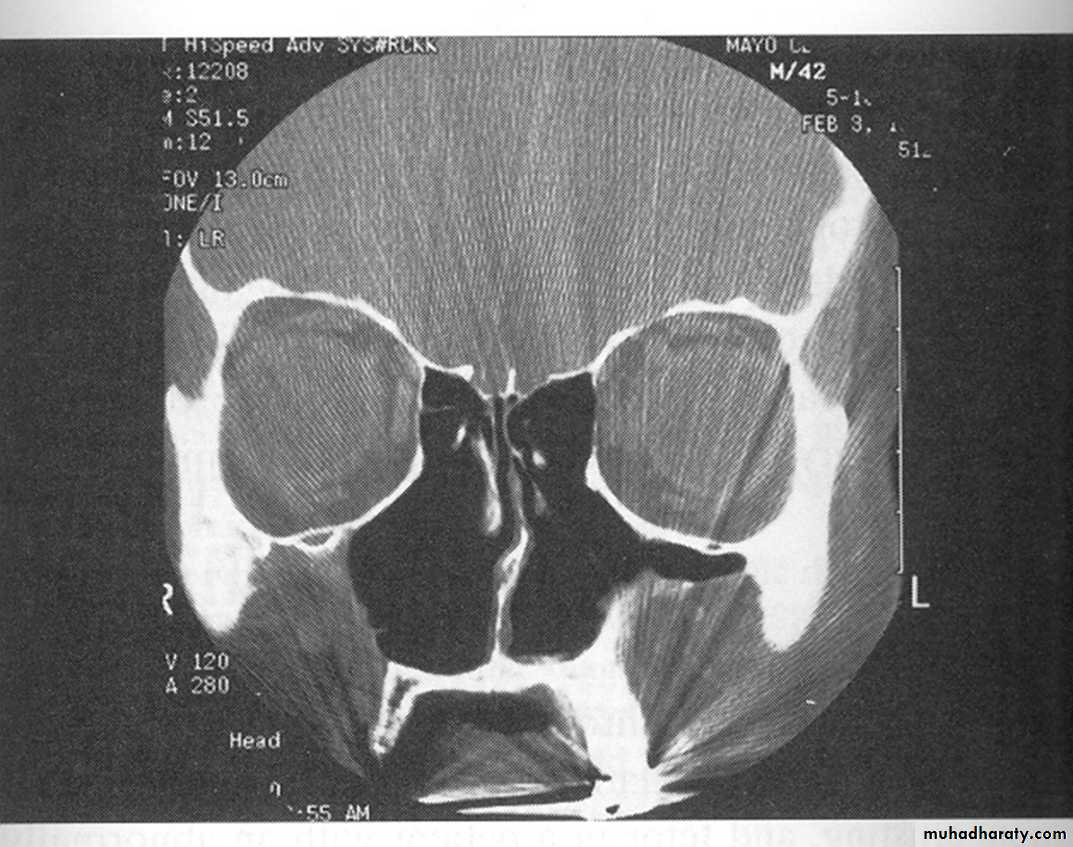

Investigations

NAR is a diagnosis of exclusion, and the aim of investigations is to identify other causes of rhinitis. IgE estimation by PRIST and RAST and skin testing can be used to indicate allergy. Radiological examination of the nose and sinuses with CT scanning may help diagnose structural abnormalities and any coexistent sinus infection.46